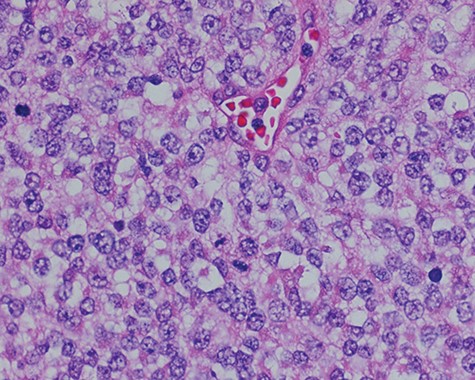

Touch prep of the excised lesion, prepared intraoperatively, showed loosely cohesive malignant neoplastic cells with small hyperchromatic nuclei and scant cytoplasm suspicious for a small round cell tumor.

Sections of the lesion consist predominantly of sheets of poorly differentiated malignant neoplastic cells with moderately pleomorphic vesicular nuclei, clear cytoplasm, and abundant mitotic activity.

Surgical consultation revealed a deeply ulcerated cavitary-like mass with gelatinous content. The excised mass, covered by an ellipse of skin, was 5.0 cm × 3.5 cm × 3.5 cm. On section, the mass was 2.5 cm in diameter, pale tan-white with red–brown areas of discoloration. Intraoperative touch preparation of the lesional cut surface was suspicious for small round blue cell (SRBC) tumor (Fig. 3). Microscopic sections of the lesion consisted predominantly of sheets of poorly differentiated malignant neoplastic cells with moderately pleomorphic vesicular nuclei, scant clear cytoplasm and abundant mitotic activity (Fig. 4). The neoplasm extended to the inked surgical margins of resection.